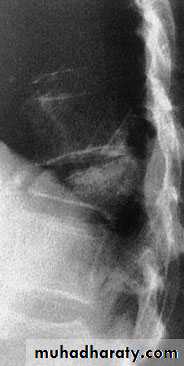

Thoracic Spine X Ray

Lateral radiograph

A/P radiographIn general a typical vertebra consists of :